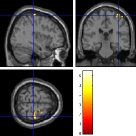

Once the reduced FOV images are available, the proposed pMRI 4D-UWR-SENSE algorithm and its early UWR-SENSE version have been utilized in a final step to reconstruct the full FOV EPI images and compared to the mSENSE Siemens solution. For the wavelet-based regularization, dyadic Symmlet orthonormal wavelet bases [48] associated with filters of length 8 have been used over resolution levels. The reconstructed EPI images then enter in our fMRI study in order to measure the impact of the reconstruction method choice on brain activity detection. Note also that the proposed reconstruction algorithm requires the estimation of the coil sensitivity maps (matrix in Eq. (2)). As proposed in [4], the latter were estimated by dividing the coil-specific images by the module of the Sum Of Squares (SOS) images, which are computed from the specific acquisition of the -space centre (24 lines) before the scans. The same sensitivity map estimation is then used for all the compared methods. Fig. 5 compares the two pMRI reconstruction algorithms to illustrate on axial, coronal and sagittal EPI slices how the mSENSE reconstruction artifacts have been removed using the 4D-UWR-SENSE approach. Reconstructed mSENSE images actually present large artifacts located both at the centre and boundaries of the brain in sensory and cognitive regions (temporal lobes, frontal and motor cortices, …). This results in SNR loss and thus may have a dramatic impact for activation detection in these brain regions. Note that these conclusions are reproducible across subjects although the artifacts may appear on different slices (see red circles in Fig. 5). One can also notice that some residual artifacts still exist in the reconstructed images with our pipeline especially for . Such strong artifacts are only attenuated and not fully removed because of the high level of information loss at .

| mSENSE | 4D-UWR-SENSE | ||

| Axial |  |

|

|

| Coronal | |||

| Sagittal | |||

| Axial |  |

|

|

| Coronal | |||

| Sagittal |